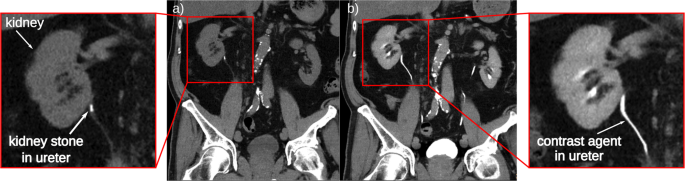

In Fig. 3, the reconstructed slices through the kidney and the calculated KES iodine and inverse KES calcium slices are presented. In both the unfiltered CT (Fig. 3a) and the filtered CT slice (Fig. 3b) the iodine filled blood vessels inside the kidney are visible. Additionally, the diffusion of the iodine into the tissue can be seen as slightly contrasted areas. The attenuation coefficient µ of the calcium-based kidney stone (0.2105 ± 0.0151 1/mm), which is positioned on the surface of the kidney, is very similar to the attenuation of the contrast agent (0.2184 ± 0.0100 1/mm). As the kidney stone would be located inside the renal pelvis or ureter in a patient setting, the iodine contrast agent and the kidney stone are expected to be in the same area, while similar CT values would make it impossible to separate both materials. After K-edge subtraction of the two slices (Fig. 3c), every material but iodine is eliminated from the resulting image so that the blood vessels can be clearly identified. In the inverse KES (as described in the Methods section), the kidney stone becomes visible whilst the iodine filled blood vessels are inverted (Fig. 3d). The use of the KES subtraction method for CT allows to separate iodine contrast agents and calcifications. This is especially helpful in clinical diagnostics when looking for kidney stones in contrast enhanced CT.

Reconstructed CT slices of porcine kidney with kidney stone (indicated by the red arrow) in transverse slice orientation (slice thickness: 70 µm). (a) Unfiltered CT slice, where both the blood vessels (indicated by the yellow arrows) and the kidney stone are visible; (b) iodine filtered CT slice, where the attenuation of the iodine in the blood vessels is reduced, yet it is not possible to distinguish the two materials; (c) in the KES image only structures containing iodine contrast agent stay visible, the kidney stone is eliminated from the image; (d) when performing inverse KES, the iodine is inverted so that the kidney stone can be clearly identified. The gray scales of the unfiltered and filtered CT slices show the absorption values in 1/mm whilst the KES slices show the differences in absorption.